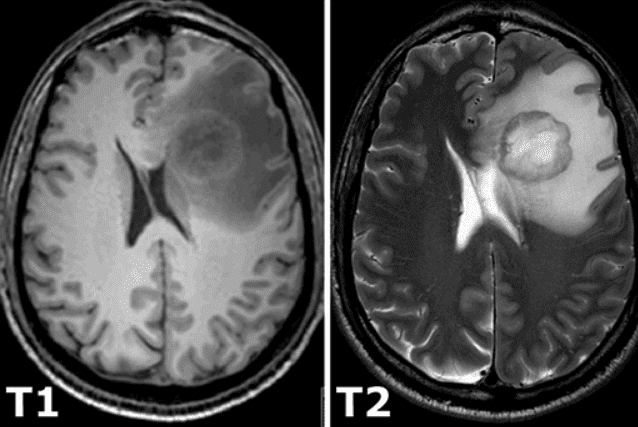

所有恒定磁化强度都通过一个额外的射频脉冲旋转到另一个平面,该脉冲足够强并且施加的时间足够长以倾斜磁化强度。励磁后,磁化立即在另一个平面上旋转。旋转磁化在接收线圈中产生 MR 信号。然而,MR 信号由于两个独立的过程而迅速衰减,这两个过程会降低磁化强度,从而导致返回到激发前存在的稳定状态,从而产生所谓的T1 图像和 T2 磁共振图像. T1 弛豫与原子核对其周围的能量过剩有关,而 T2 弛豫是指各个磁化矢量开始相互抵消的现象。上述现象是完全独立的。因此,不同的强度代表不同的组织,如下图所示: